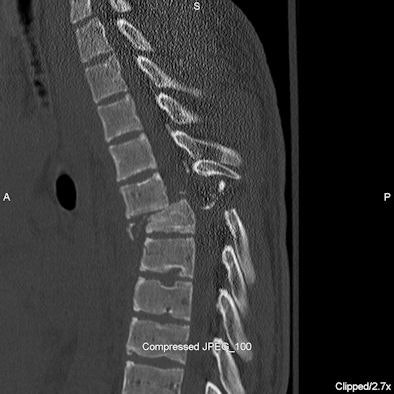

Twenty-one children had spinal fractures, and five children had spinal cord injuries.

| Spinal cord injury: Sagittal CT (above) and short-tau inversion recovery (STIR) MRI (below) images of the thoracic spine of a 16-year-old male who was found in a ditch by a passerby after a rollover ATV accident. He suffered compression fractures of T5 and T6 with anterior subluxation of T5 over T6 with intraspinal fracture fragments and severe spinal cord injury. Spinal cord showed near complete transaction at this level. Subsequently, he developed dural cerebrospinal fluid leak at T5-6 level. He also suffered fracture of C2 vertebra and multiple facial bone fractures. He was not wearing a helmet. On a recent follow-up eight months after the injury, there is no improvement in paraplegia. All images courtesy of Dr. Chetan Shah. |